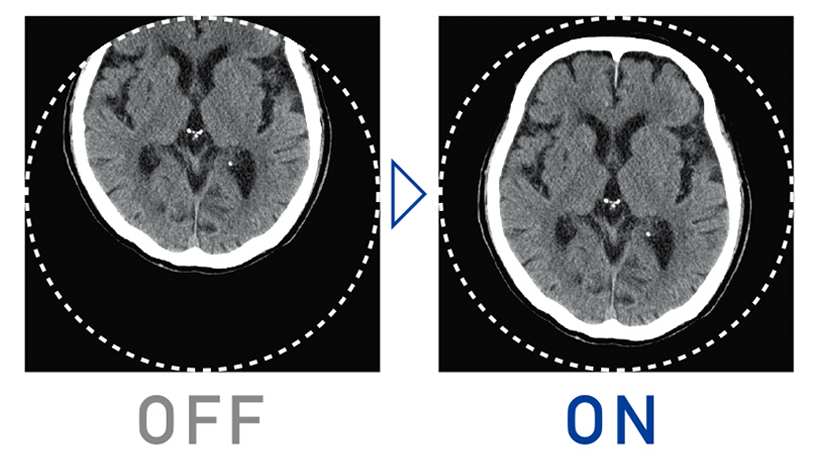

ノイズ低減技術である逐次近似処理(Intelli IP)をルーチン検査で使いやすくする為に、画像処理速度を従来より50%向上させました。また、ノイズ低減の強度も7段階から選択でき、ご施設の運用ポリシーに沿った適切な被ばく線量と、画像ノイズ低減やアーチファクト低減による高画質な画像を提供します。

また、円背の被検者などで有効視野からはみ出してしまった場合でも、最大有効視野内であれば、再撮影することなく、画像再構成が可能です。